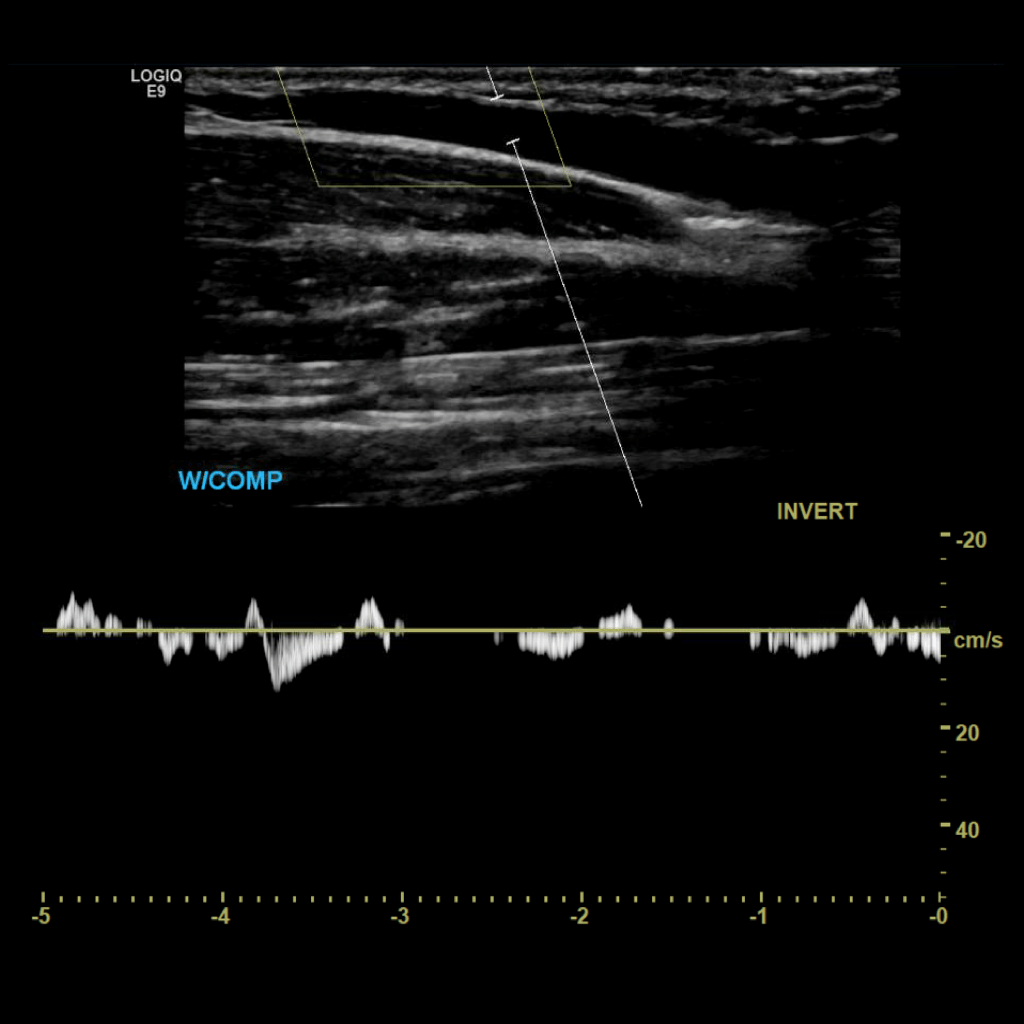

Scan the ulnar veins in grey scale, compression, color doppler and spectral doppler